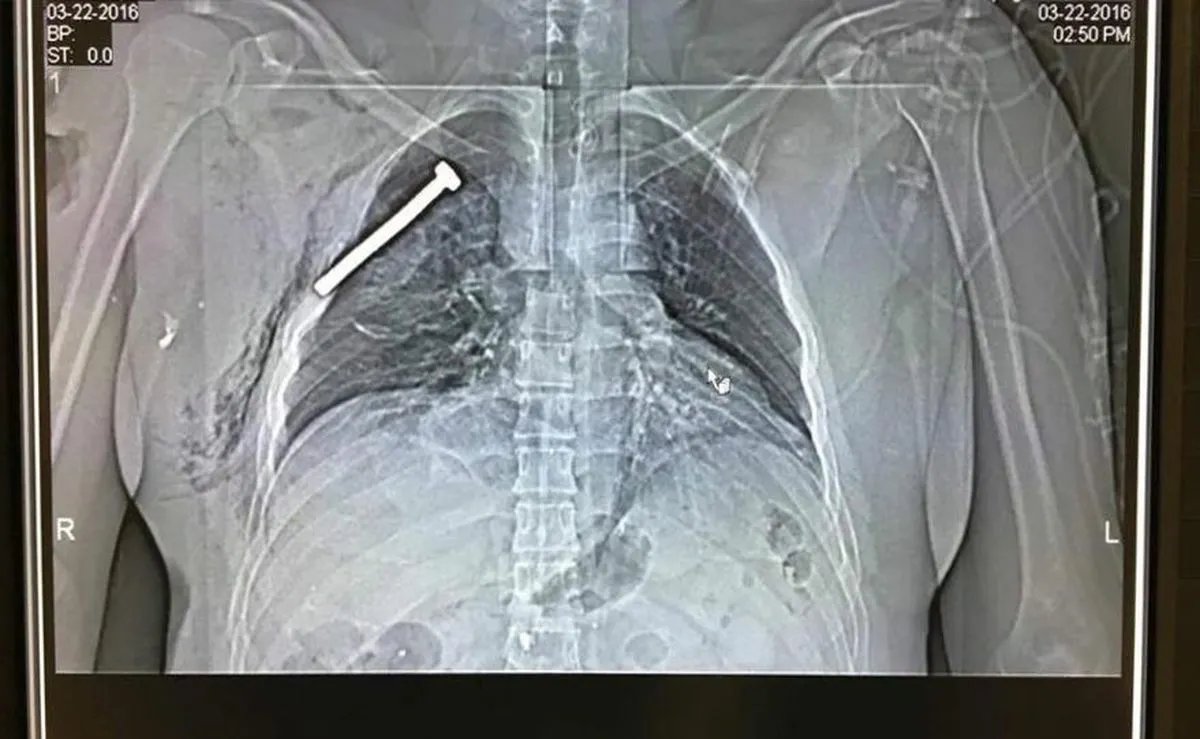

22 marca 2016Dwa wybuchy na lotnisku Zaventem w Brukseli. Według najnowszych informacji, policja otworzyła ogień do ludzi krzyczących po arabsku. Wtedy wybuchły dwie bomby. Później eksplodował ładunek w metrze. Liczba ofiar zamachów terrorystycznych w Brukseli wzrosła już do co najmniej 36. Wśród rannych jest też trzech Polaków.